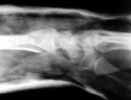

This 30 year old man sustained comminuted fracture shaft and undisplaced fracture neck of humerus. He has also technically compound fracture Distal Radius with intra-articular extension, but joint surface is congruent in the same upper limb. At present wound debridement POP immobilisation done. Options for management in this case? I am inclined to continue conservative management.

Presently I did closed reduction and Plaster cast immobilisation. Post reduction Xrays are attached. Do you think this will slip subsequently ?